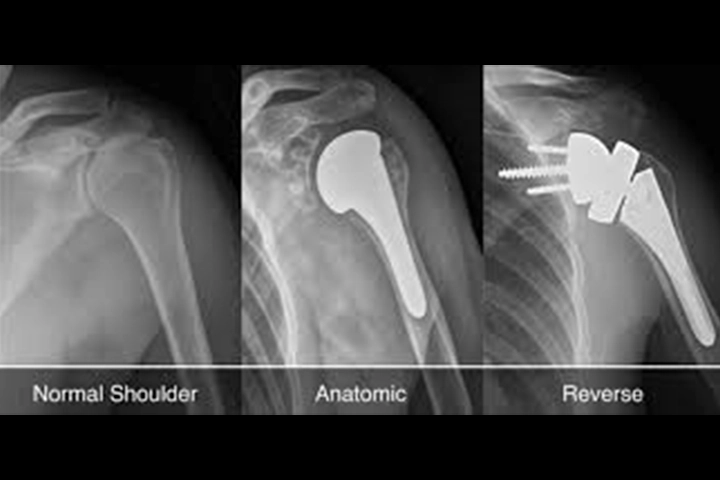

There are several different types of shoulder replacements. The usual total shoulder replacement involves replacing the arthritic joint surfaces with a highly polished metal ball attached to a stem, and a plastic socket.

The more recent type of shoulder replacement is called reverse total shoulder replacement. Reverse total shoulder replacement is used for people who have:

- Completely torn rotator cuffs and

- The effects of severe arthritis (cuff tear arthropathy) or

- Had a previous shoulder replacement that failed